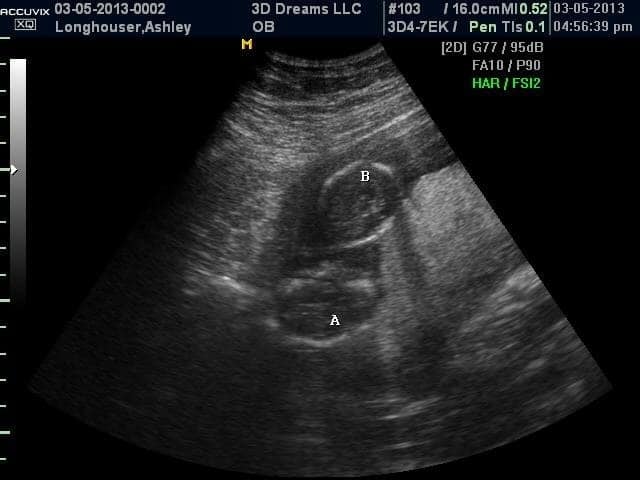

- Ultrasound Photos at 13 Weeks Pregnant With Twin

Ultrasound Photos at 13 Weeks Pregnant With Twin